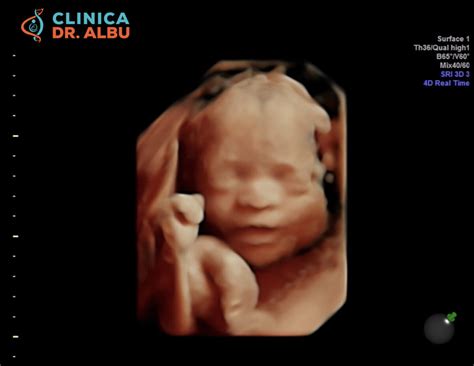

Ecografia morfologică de trimestru I este o investigație ecografică non-invazivă, realizată transvaginal, între săptămânile 11 și 13, 6 zile de gestație. Aceasta presupune o analiză detaliată a tuturor structurilor fetale vizibile, oferind informații valoroase despre dezvoltarea embrionului.

- Dezvoltarea structurilor fetale: Medicul examinează diferite părți ale corpului fătului pentru a se asigura că s-au dezvoltat corespunzător.